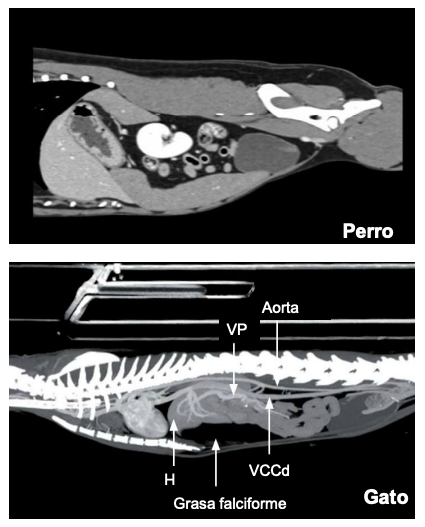

Topogradía abdominal del perro: Tac o TC del tejid blando, vista dorsal

Generalmente las imagenes de tac están espejadas

En gato el bazo siempre esta en la izquierda, el perros la cola puede estar a la derecha

IMAIOS para repasar imagenes de tac